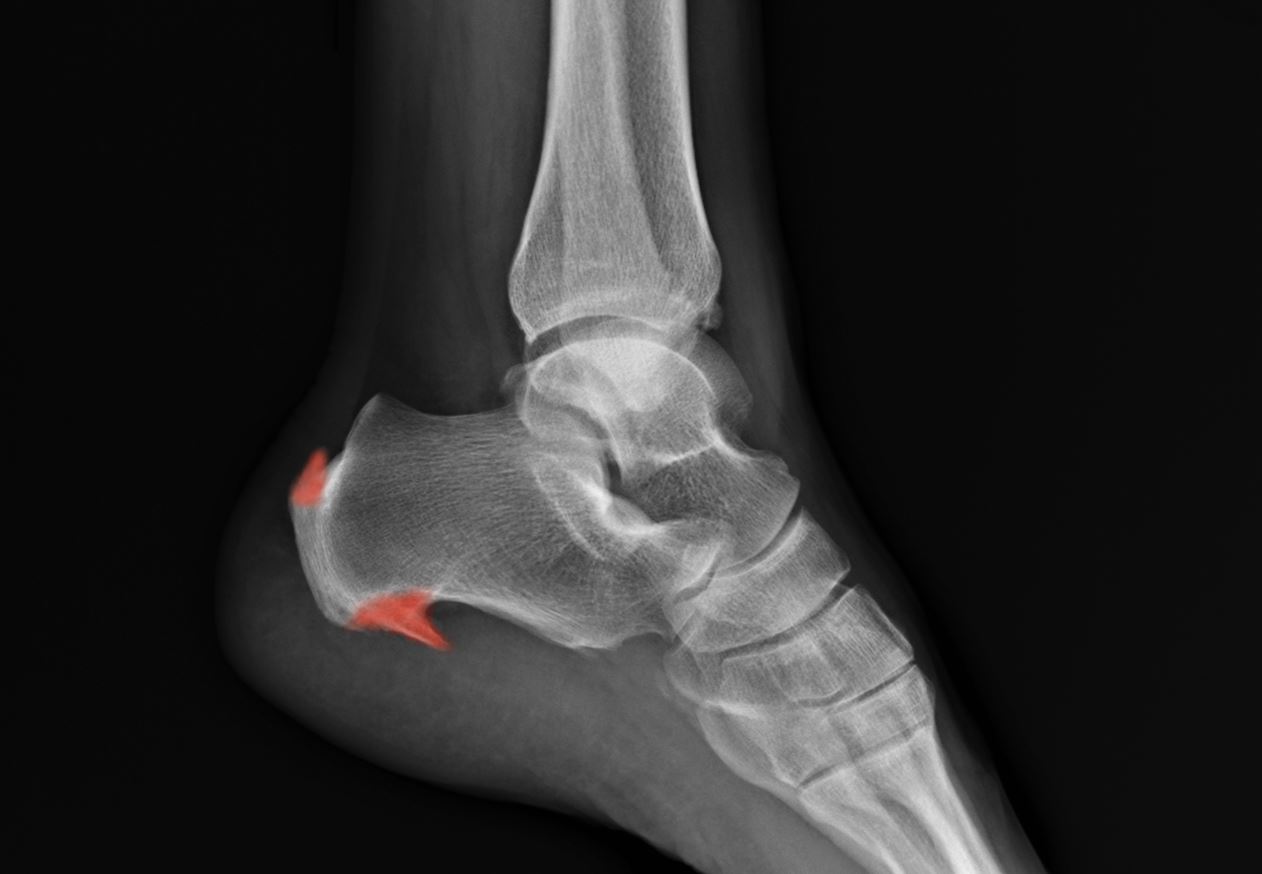

Heel spurs

Heel spurs are bony growths that form on the bottom or the back of the heel bone. They often occur as a result of long-term plantar fasciitis or Achilles tendinitis. Heel spurs are our body’s natural response to tendon stress, and they are usually not the main cause of your heel pain. The symptoms of heel spurs are largely similar to plantar fasciitis or Achilles tendinitis, depending on where the spurs are at.

Heel spurs are normally found at the back or the bottom of the heel bone.